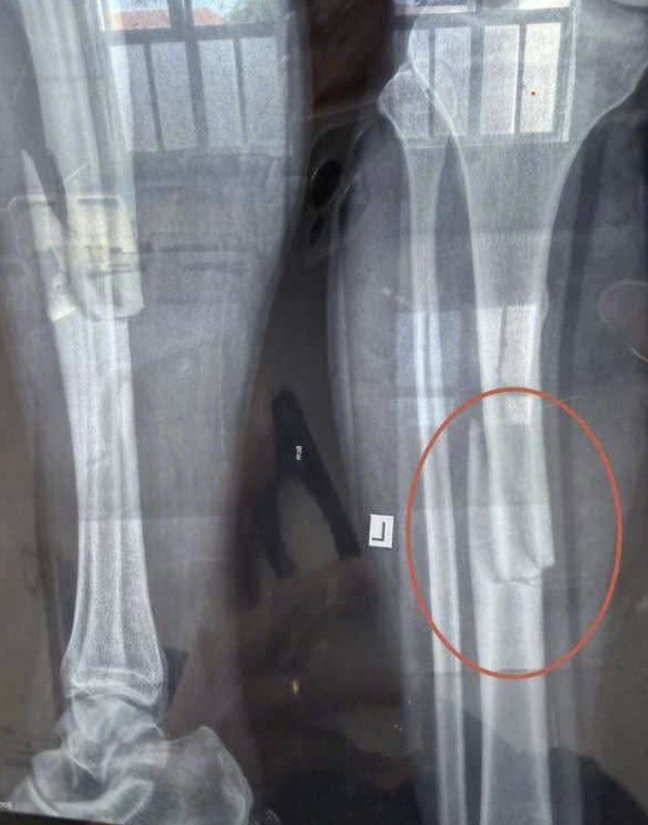

KCN Phước Đông: TNLĐ trong lúc làm vjệc khiê’n nam thanh niên g::ãy chân. Cân nhắc khi xem